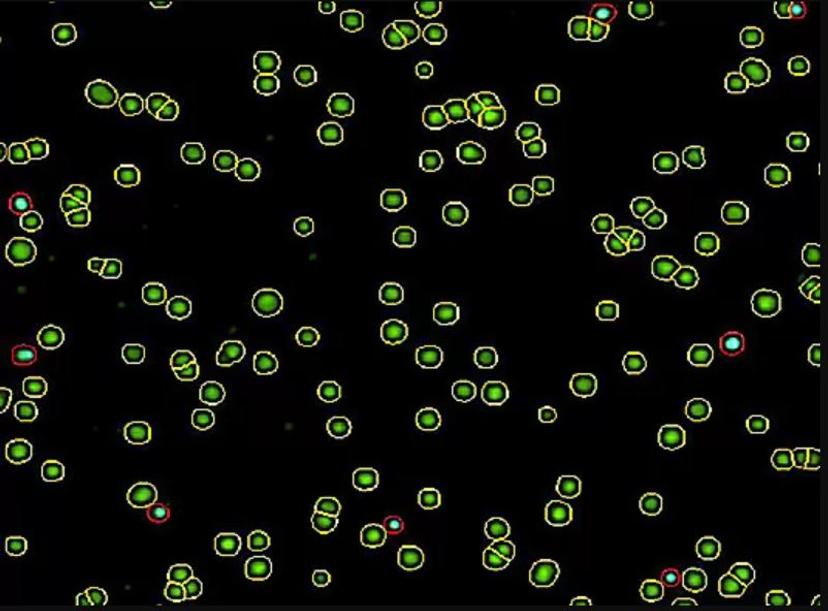

The NC-View™ software enables users to conveniently view the fluorescent data image along with a more in-depth visual analysis of this data.

In the viewer, you can turn individual LED channels on and off to inspect cells—all cells are captured in the green channel, dead cells in the blue channel, and both can be seen in the merged view. You can visualize live and dead cells even more clearly, which are circled with yellow and red, respectively for easy cell verification.